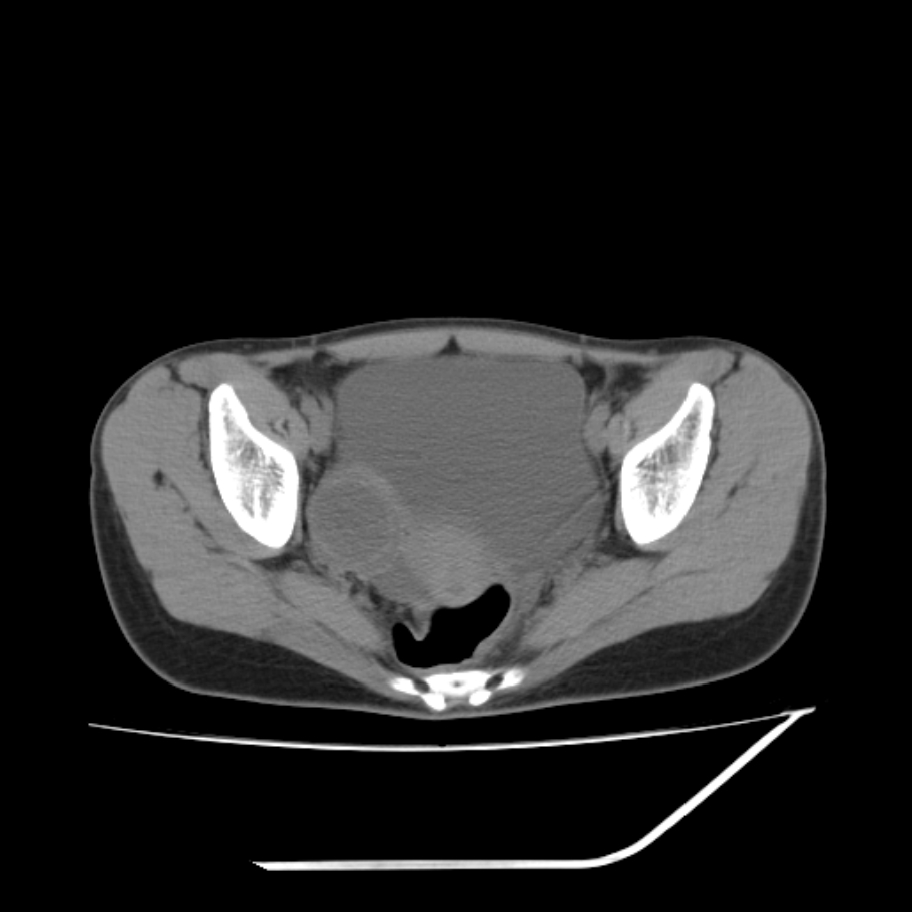

女,25岁。偶尔有右下腹不适感,余无明显异常。(结婚半年),囊壁较厚,是卵巢囊肿吗?

右侧卵巢区椭圆形囊性肿物,内壁光滑 无分隔。直肠子宫间隙内有少量积液征象。结合临床考虑卵巢巧克力囊肿,还要问问有没有痛经,本例ct怎么没有灌肠?要是灌肠或前一前口服造影剂,起码可以和肠管区别开

b超示:囊实性占位,畸胎瘤?临床有痛经。

巧克力囊肿

考虑右侧卵巢囊性占位性病变(巧克力囊肿?),盆腔积液有不排除宫外孕可能,请结合临床和b超。